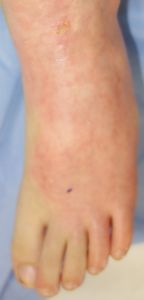

2016年5月1日,料理の手伝いをしていて椅子に立ってカレーの鍋をかき回していて足を滑らせて転倒し,落ちてきた鍋の熱湯で両側大腿,左下腿,左足背に熱傷受傷。〇〇大学△△病院に救急搬送されて形成外科入院となった。石鹸洗浄後にバラマイシンとフィブラストスプレー®で治療。5月31日,担当医からいきなり「右大腿は深い3度熱傷のため,直ちに手術が必要。来週火曜日に手術なので今日採血します」と説明された。それまで手術の話は一切なかったため,両親は不信感をいだき,ネットで「熱傷 植皮しない」と検索し,筆者にメールで相談。6月17日,同院退院後に当科を受診。

6月17日,当科受診。左下肢は広範な2度熱傷,左大腿は小範囲(直径4センチ足らず)の3度熱傷だった。右大腿はハイドロコロイド被覆材で被覆し,左下肢は穴あきポリ袋で覆って吸収シートで覆う方法で治療。

左下肢の状態のみ供覧。右大腿の3度熱傷は小範囲なので無視。